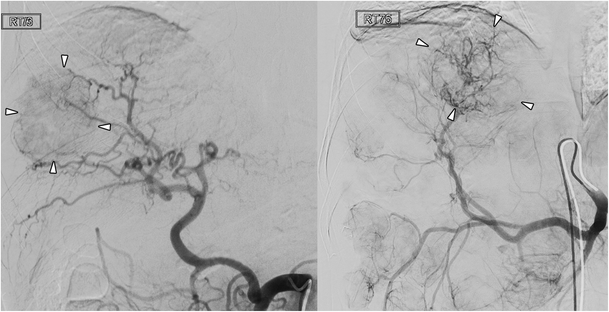

There was no statistically significant difference regarding the image quality between the two cohorts according to both readers (p = 0.82 and p = 0.75, respectively) using the provided four-point grading score for the visibility of hepatic arteries. Both readers rated the majority of celiac arteriograms in both cohorts as perfect (category 1) (Fig. 2). No celiac arteriogram was rated as category 4 (Table 5). Cohen’s kappa showed a substantial agreement between both readers (κ = 0.76 and κ = 0.66 for the old and new platforms, respectively, p < 0.01). A detailed distribution of image quality scores is shown in Table 5.

Fig. 2

Celiac arteriogram during TACE in two patients with neuroendocrine tumour. Left panel was acquired on the preceding imaging platform and the right panel on the new imaging platform. Both arteriograms were of diagnostic quality, showing the tumour-feeding arteries and the tumour blush (arrowheads). However, the new imaging platform resulted in a significantly lower radiation exposure during the acquisition of the celiac arteriogram